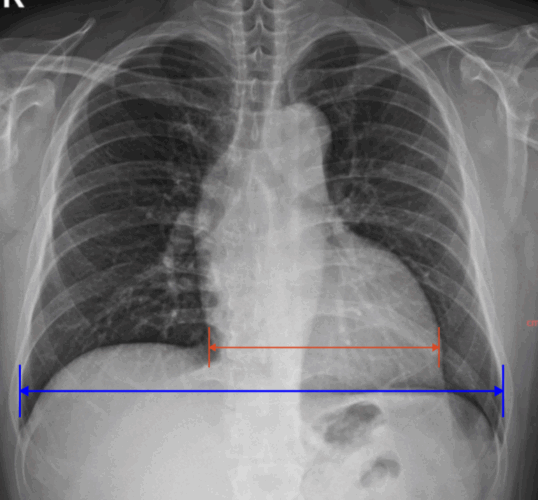

Chest X-ray

Principle

– 조직별 X선 흡수 차이를 영상화하여 흉부 구조를 확인

Key Features

– 검사 시간이 매우 짧고 상대적 저선량

– 심장질환 진단의 특이도는 낮아 타 검사와 종합 판단 필요